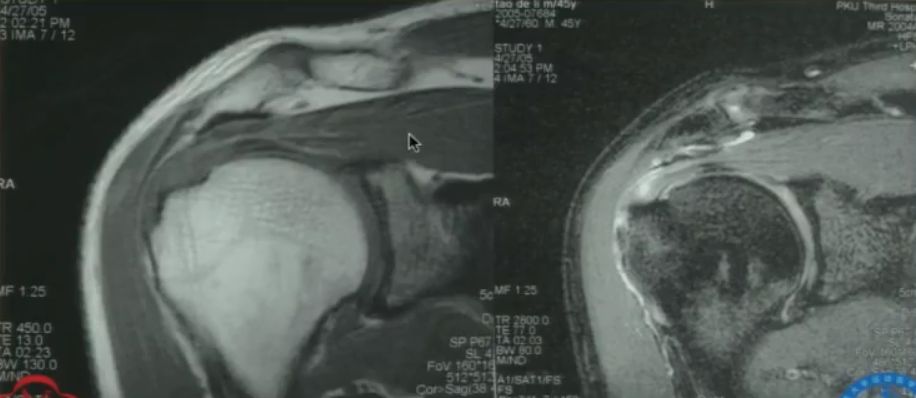

重点 重点一:肩袖的解剖特点 肩袖是包绕在肱骨头周围的一组肌腱复合体,形成一个类似于“袖口”状的结构,如图1所示。前方为肩胛下肌腱,上方为冈上肌腱,后方为冈下肌腱和小圆肌腱,这些肌腱将肱骨头稳定于肩胛盂上,对维持肩关节的稳定和肩关节活动起着极其重要的作用。 图1 肩袖解剖示意图 重点二:肩袖的力偶结构 肩袖的运动功能主要通过两对力偶完成:肩胛下肌VS冈下肌、小圆肌;冈上肌VS三角肌。 ??(1)肩胛下肌VS冈下肌、小圆肌 肩关节前方的肩胛下肌与后方的冈下肌、小圆肌形成一对力偶(如图2所示),该力偶能够将肱骨头固定于肩胛盂上,维持肩关节的稳定性,同时可以完成肩关节的旋前与旋后运动。 图2 力偶-肩胛下肌VS冈下肌、小圆肌 ??(2)冈上肌VS三角肌 单纯依靠三角肌的外展提拉作用,无法完成肩关节外展运动。冈上肌的作用力有向下方向的垂直分解力(如图3所示),该力能够下压肱骨头,为肩关节外展提供支点,使得肱骨能够围绕该支点完成外展运动。 图3 力偶-冈上肌VS三角肌 重点三:肩袖损伤的机制 肩袖损伤机制可分为两大类:第一类是有明确的外伤史导致肩袖发生急性撕裂;第二类是慢性退变性改变,此类临床最为常见。下面重点介绍慢性退变性肩袖损伤的发病机制。 肩关节前屈、外展时,肱骨大结节与肩峰前三分之一、喙肩韧带和肩锁关节发生撞击,导致肩峰下滑囊炎等退变性改变,日积月累逐渐发展为肩袖撕裂。 根据此理论可以对肩峰形态进行划分,拍摄肩胛骨Y位影像(如图4所示): I型肩峰下表面平滑; II型肩峰下表面为弧形; III型为钩形肩峰。 在肩峰撞击这一始动因素下,随着患者年龄增长,肩袖组织退变,日常上肢上举动作过多等导致肩峰撞击次数增多,最终导致肩袖损伤。 图4 肩峰形态分型 重点四:肩袖损伤的临床表现 外伤导致肩袖撕裂的患者一般均有明确的外伤史。而慢性退变性肩袖损伤的患者,其年龄较大,多为劳损性退变导致的损伤,患者肩关节功能障碍及疼痛症状一般持续时间较久。患者最典型的两个临床表现是“疼痛”+“力弱”。患者主诉肩关节疼痛剧烈,疼痛区域集中在肩峰前外缘、肱骨大结节区域。患者力量减弱同时表现为耐力较差,如无法长时间维持上肢上举动作等。 重点五:肩袖损伤的体格检查 ??(1)疼痛弧 疼痛弧是肩袖损伤患者的临床表现之一。患者肩关节外展至60-120°时会出现明显疼痛表现,继续外展超过这一角度范围时,疼痛消失(如图5所示)。出现该表现的原因是,在肩关节外展至60-120°范围时,肱骨大结节与肩峰发生撞击产生疼痛,继续外展超过这一角度范围时,肱骨大结节不再与肩峰发生接触,疼痛消失。 图5 疼痛弧示意图 ??(2)Neer征 检查者一手固定肩胛骨,另一手保持肩关节内旋位,使患者拇指尖向下,然后使患肩前屈过顶,如果诱发疼痛,即为阳性(如图6所示),机理是人为的使肱骨大结节与肩峰前下缘发生撞击,从而诱发疼痛。 图6 Neer征 ??(3)冈上肌抗阻试验-Jobe’s试验 上肢外展90°前屈30°拇指向下,上肢位于肩胛骨水平,类似于倒水杯动作(如图7所示),故该试验又名空杯试验,检查者用力向下按压上肢,患者抵抗,与对侧相比力量减弱或者患者出现疼痛,提示肩袖病变或者冈上肌腱病变或者撕裂。 图7 Jobe’s试验即空杯试验 ??(4)落臂征 将患者患肢被动上举,然后令其缓慢放下,如果不能慢慢放下,出现突然直落到本侧,为本试验阳性,说明冈上肌腱完全撕裂。 ??(5)外旋抗阻试验 患者肩关节处于内收位,屈肘90°,肘部处于体侧并夹紧,让患者抵抗阻力将双肩外旋(如图8所示)。如力量明显减弱即为阳性。提示冈下肌和小圆肌肌腱损伤。 图8 外旋抗阻试验 ??(6)Lift-off试验 患者将手背置于下背部手心向后,嘱患者将手抬离背部(如图9所示),检查者给予抵抗阻力,不能完成动作为阳性,提示肩胛下肌损伤。 图9 Lift-off试验 ??(7)压腹试验 患者将手置于腹部,手背向前,屈肘 90 度,肘关节向前。检查者将患者手向前拉,而嘱患者抗阻力做压腹部的动作。患者在将肘向前时不能保持手压腹的力量或肩后伸则为阳性,提示肩胛下肌损伤。 图10 压腹试验(左侧为阴性,右侧为阳性) 重点六:肩袖损伤的辅助检查 ??(1)X线检查 可见到大结节硬化,肩峰前缘骨赘囊性变,肩峰、肱骨头间隙变窄等表现(如图11所示)。 图11 肩袖损伤的X线表现 ??(2)MRI检查 进行MRI检查时,尤其要注意MRI扫描切割平面的确定,应该选择斜矢状位(垂直于肩胛骨平面)及斜冠状位(平行于肩胛骨平面)进行切割(如图12所示),这样才能完整的显示冈上肌腱、冈下肌腱。尤其要注意观察T2压脂像,该显像序列对于观察肩袖损伤最为重要。 图12 斜冠状位和斜矢状位切割 肩袖损伤的MRI表现主要有三点:①信号增高;②肌腱厚度增粗;③肌腱连续性中断。以上三条只要出现一个,就可以确定有肩袖撕裂的MRI表现(如图13所示)。 图13 肩袖撕裂的MRI表现 ??(3)CT肩关节造影检查 CT肩关节内造影检查适用于MRI检查禁忌的患者,该方法向关节腔内注入造影剂,如冈上肌腱存在全层撕裂,则表现为断裂部位造影剂充盈缺损(如图14所示)。但注意该方法只能显示肩袖全层撕裂,对于部分撕裂,则可能造成漏诊。 图14 肩关节造影示冈上肌腱断裂 重点七:肩袖损伤与肩周炎的鉴别诊断 临床诊疗中,肩袖损伤患者极易被误诊为肩周炎进行治疗。下面列举两者的鉴别诊断要点: 其中最重要的鉴别点是活动范围,肩袖撕裂患者其肩关节主动活动受限,被动不受限;而肩周炎患者其肩关节活动范围主动、被动均明显受限。尤其需要注意肩关节的外旋活动,如患者肩关节外旋活动正常,则基本可以排除肩周炎。 总结 肩袖损伤的诊断,要结合患者症状、体格检查和影像学结果进行综合诊断,一定要注意对患者肩关节主动、被动运动范围的检查,切勿将肩袖损伤误诊为肩周炎,延误治疗时机。